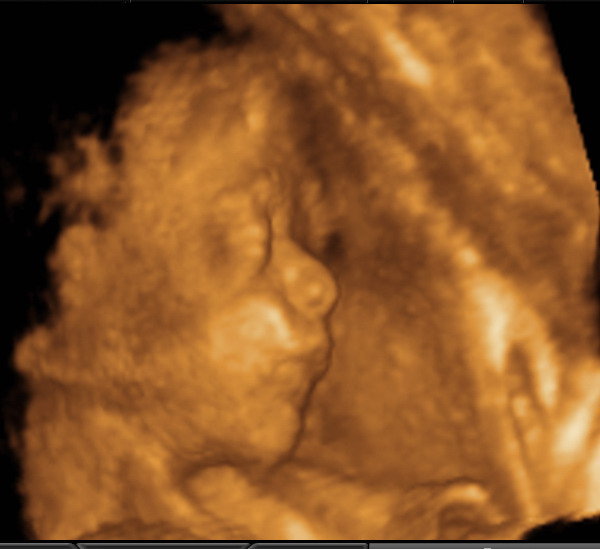

voltunk pénteken 4D-s uhn a kleopátra házban.szuper élmény volt,bár szegény párom sajna lemaradt az elejéről ,3om sarokkal a cél előtt belementek hátulról és papírokat töltögettek....

Rakok fel Vikiről képet,most épp 785g-os a kislány ,ha így haladunk azt mondta dokinéni meghaladja a 3500g-ot.

Kép Kép

Suezika, édes a babód!!! Az enyém bezzeg végig takarta az arcát.

Suezika, mennyi idős a képen Viki? Nagyon jók a képek, annyira kislányos az arca, nagyon szép.